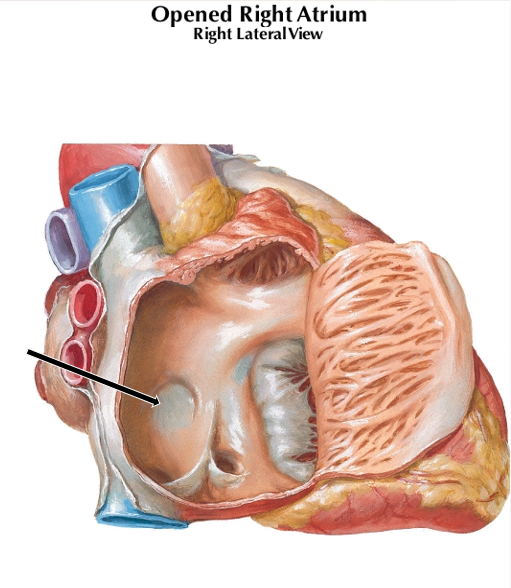

Fossa Ovalis

From embryonic Foramen Ovale

Shunt from Rt Atrium to Lt Atrium to bypass Lungs

Crista Terminalis

Separates Original Rt Atrium from smooth walled part

Pectinate muscles

Tricuspid valve

Anterior Cusp of Tricuspid Valve

Posterior and Septal Cusps